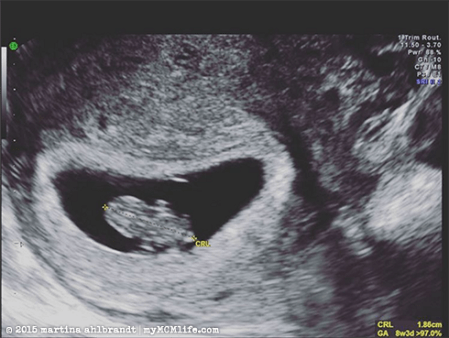

After a really long 2 weeks while we tried not to think too much about the possibility of identical twins, we saw a healthy 8.5 week old singleton on the ultrasound. Phew! Twins would have been fun but…we are already looking at having two little ones pretty close in age.